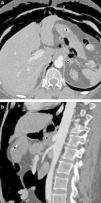

Aortitis is a pathological term designating inflammation of the aortic wall, regardless of its cause. The clinical presentation of aortitis is nonspecific and variable. Symptoms include abdominal pain, fever, and weight loss; acute phase reactants may also be elevated. Aortitis can be caused by a wide spectrum of entities, including from infectious processes to autoimmune diseases (Takayasu arteritis and giant cell arteritis are among the most common of these causing aortitis), and the prognosis and treatment of these entities vary widely. Various imaging techniques can be used to evaluate the lumen and wall of the aorta (such as multidetector computed tomography, magnetic resonance imaging, angiography, or PET-CT). This review focuses on the most common diseases that cause aortitis and on the clinical and radiological findings that are most useful for diagnosing and treating this condition appropriately.